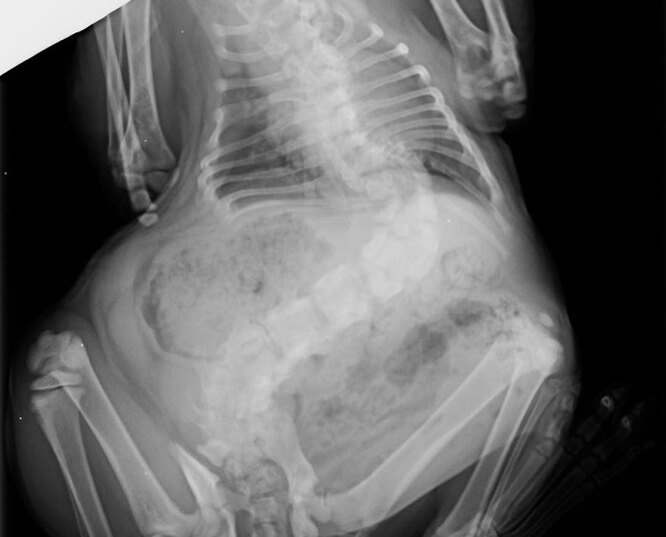

Але під час огляду лікар запідозрила у тварини проблеми серйозніші за зайву вагу. Рентген підтвердив тяжкий ступінь сколіозу, через який тіло кішки зігнулося в гачок.